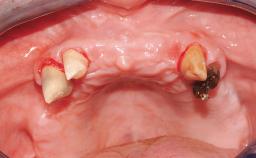

Iliac-Crest Block for Vertical and Horizontal Space Filling in the Anterior Maxilla

A 31-year-old man presented to our clinic 30 days after a motor vehicle accident in which he had suffered a dentoalveolar fracture in the anterior maxilla, including avulsion of teeth 12 and 11 and luxation of tooth 21. He was first treated on the night of the accident in a small city hospital with no oral and maxillofacial surgeon on the staff. A wired retention had been applied and the teeth repositioned to the best of the clinicians’ abilities. When he first presented to our care, the patient showed extrusion of teeth 12 and 11 associated with gingival recession due to bone loss in the anterior maxilla, and the stainless steel wires were still present.

Bone Augmentation Horizontal|Staged|Vertical

Augmentation Materials Autogenous chips|Autogenous block(s)

Bone Volume Horizontally and vertically sufficient Horizontally deficient Deficient vertically or deficient vertically AND horizontally

Soft Tissue Contour and Volume Significantly deficient